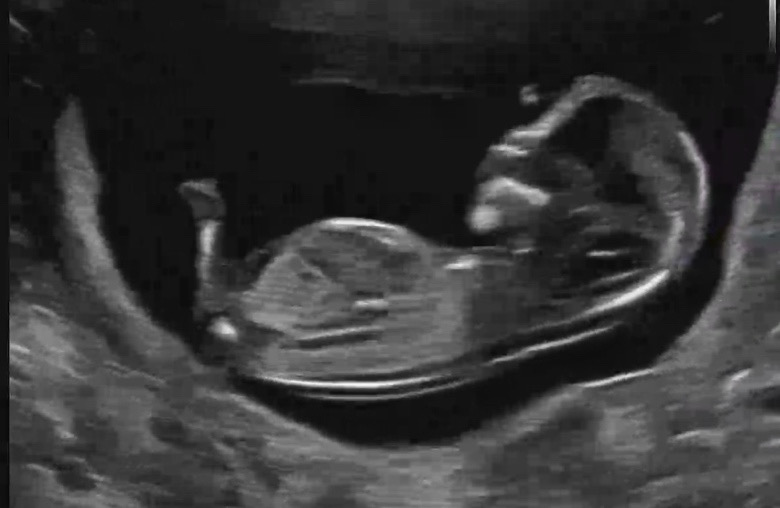

12주4일이에용 각도법이랑 초음파봐주세용!!

궁금해요궁금해요!!ㅎㅎㅎ 뭐일거같으세용ㅜ 답꼭부탁드립니당!

추가사진이에용!

딸일것같은데용 ?